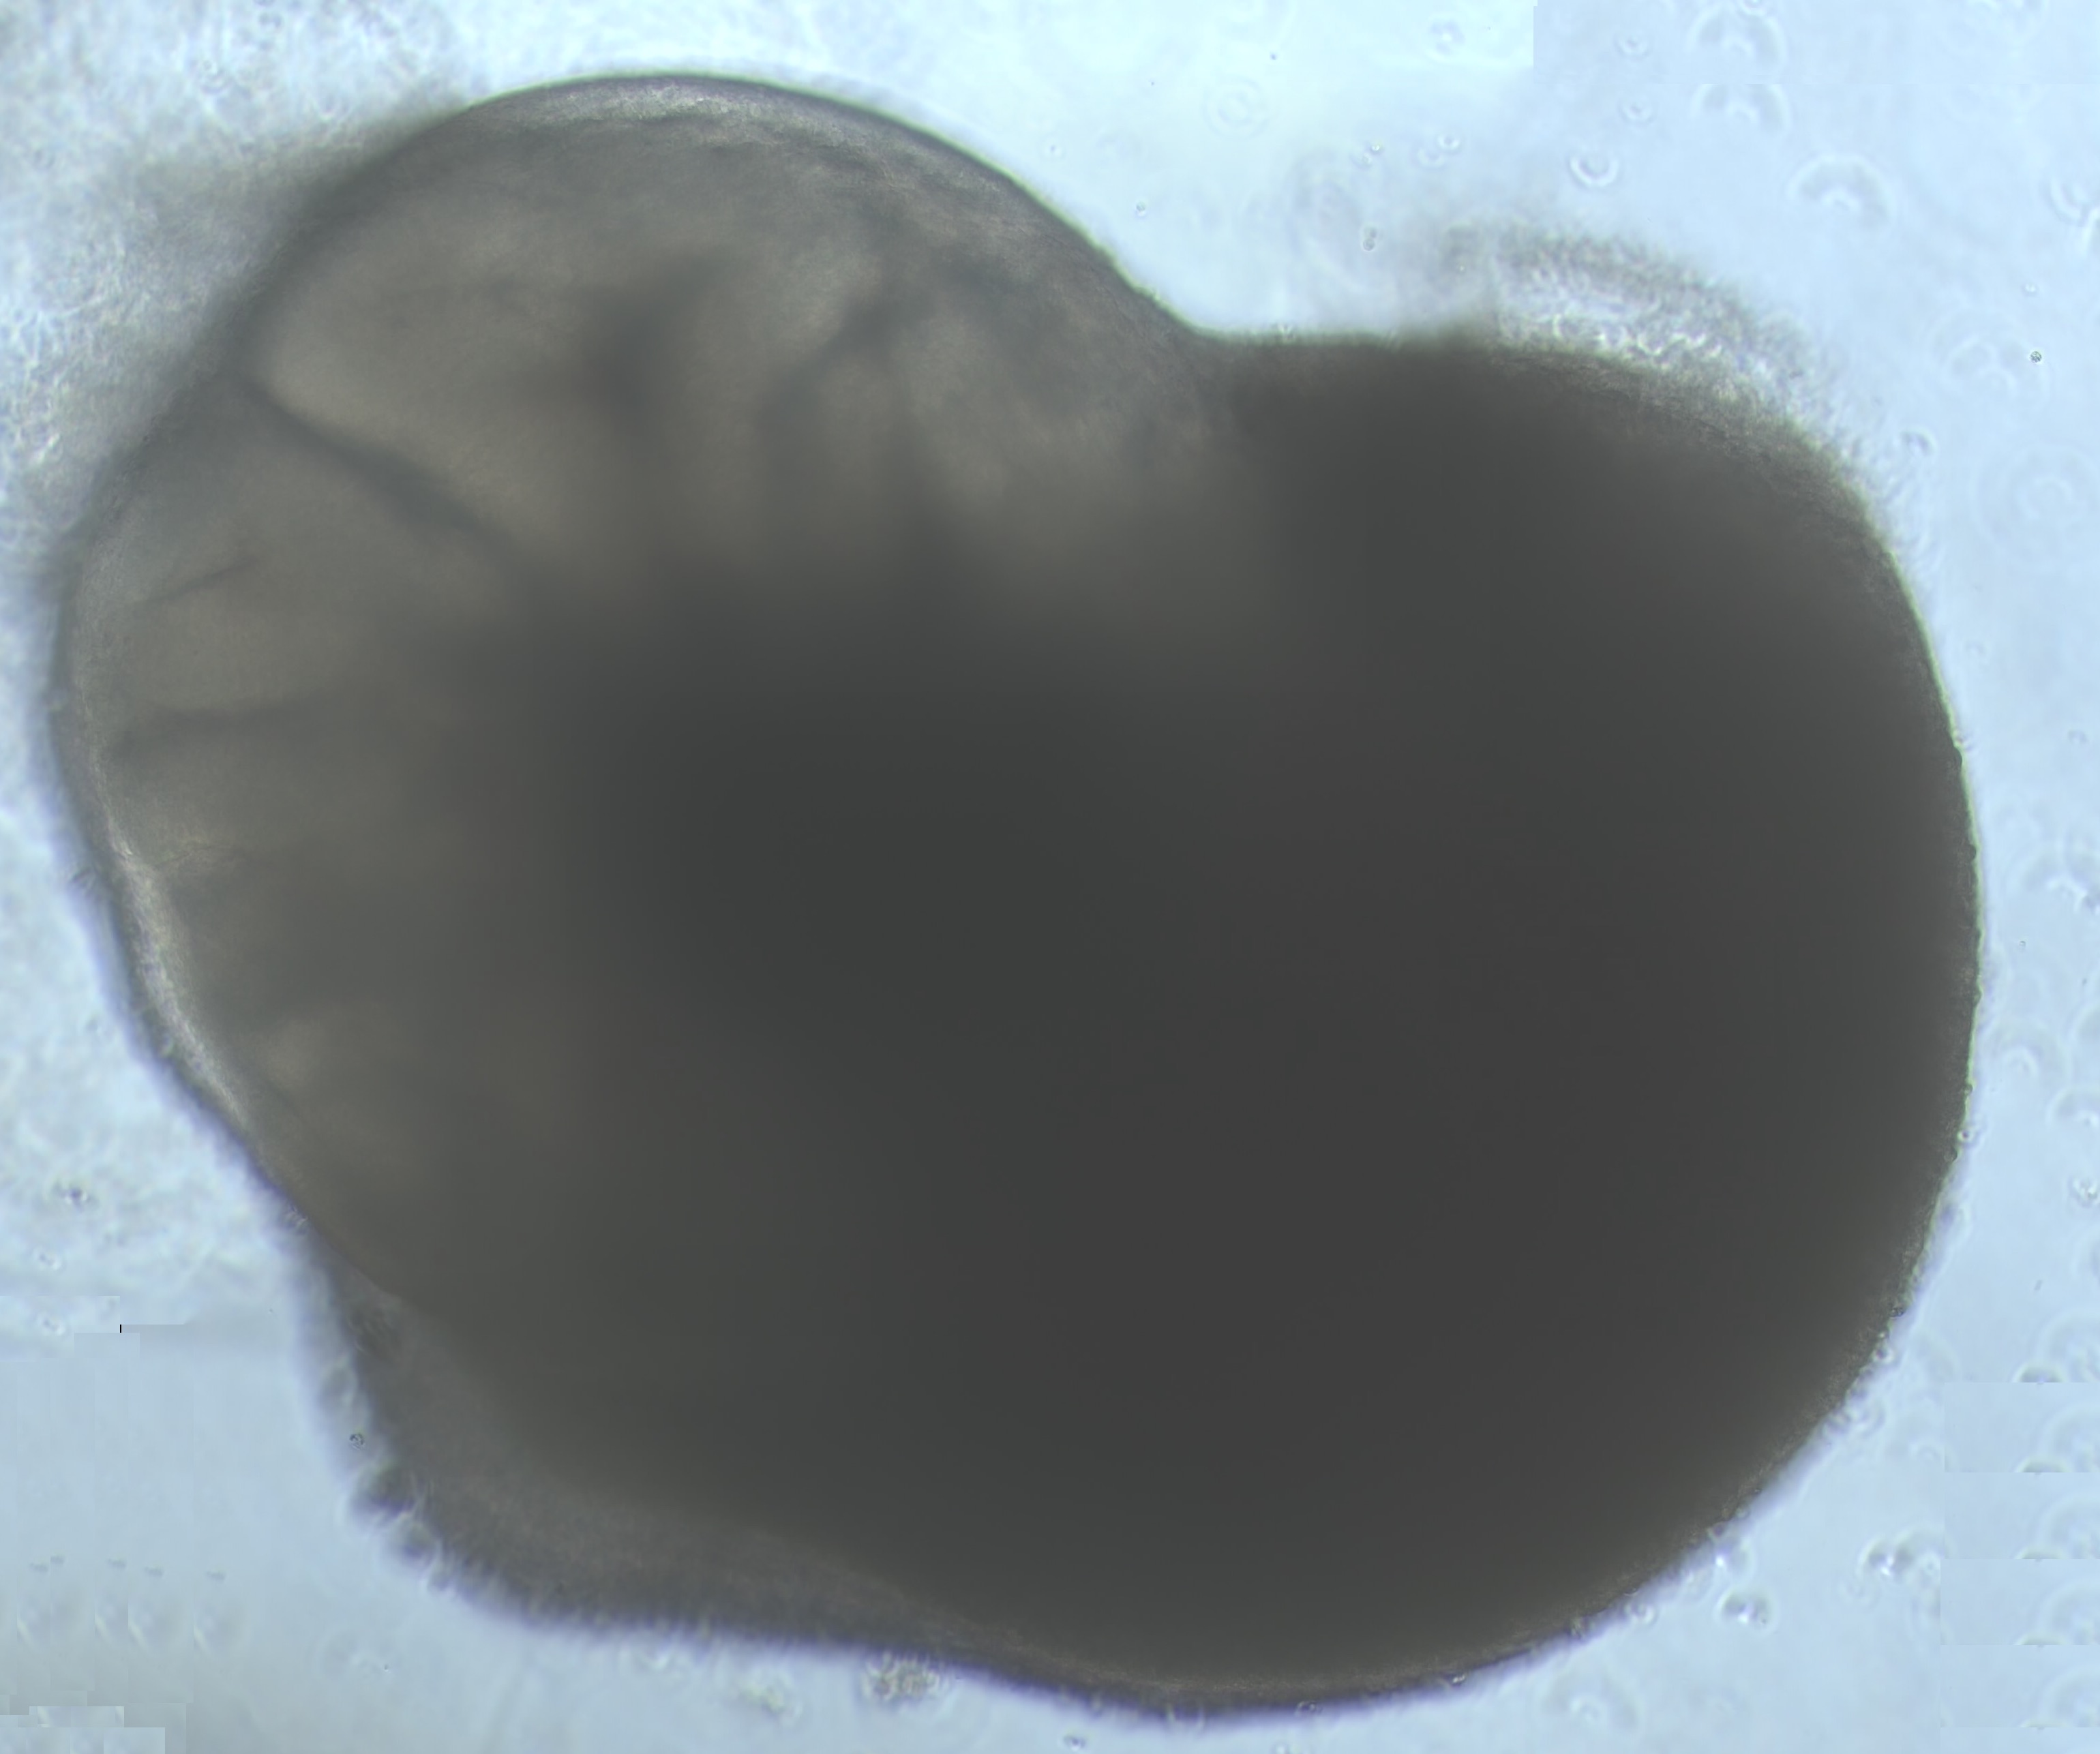

Los organoides, ya utilizados previamente en investigación, son mini-órganos con un tamaño de pocos milímetros. En general, estos se generan a partir de células madre que tienen el potencial de formar cualquier órgano humano. En este caso, se convertirán en pulmón y cerebro.

Estos mini-órganos sanos serán infectados por el SARS-CoV-2 y se evaluará su grado de deterioro. Previamente, se les habrá administrado fármacos potencialmente efectivos contra el virus y se hará un seguimiento para valorar si estos fármacos han podido evitar la replicación del virus. "Analizaremos el efecto de la infección en células humanas mediante técnicas moleculares. Además, utilizaremos fotografías microscópicas de los organoides en cada fase del proceso de infección, las cuales utilizaremos para monitorizar la evolución de la infección mediante un algoritmo de Inteligencia Artificial diseñado en colaboración con el Dr. Lao del CNAG-CRG. Así, este sistema reconocerá patrones de infección y podremos valorar rápidamente cuáles son los fármacos que están funcionando mejor", avanza la Dra. Sandra Acosta, investigadora a cargo del proyecto en el Instituto de Biología Evolutiva.